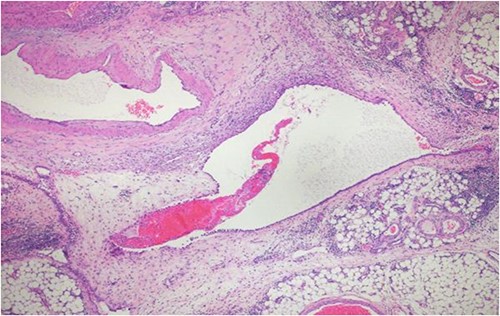

A 40-year-old Saudi, nulliparous woman, medically free with a history of leiomyoma (uterine fibroid) underwent myomectomy. She was referred to our center as a case of large abdominopelvic mass, tense ascites and pleural effusion. The patient complained of the shortness of breath, palpitation, marked abdominal discomfort and bloating as well as back pain. She reported that she first noticed the bloating 3 months prior to the visit. However, she was unable to come because of COVID-19 pandemic situation. She is a housewife; never smoked tobacco or drank alcohol, and had no history of recent travel to endemic or pandemic areas. On further investigations, a serum CA-125 was found to be elevated 492.6 U/mL (normal < 35 U/mL), whereas the concentration of other tumor markers LDH, CEA, CA19-9 and ALP was within normal ranges. Abdominal CT scan revealed a significant interval increase in the size of ascites, which caused a huge abdominal distention along with severe mass effects on the abdominopelvic organs, which have been displaced posteriorly as shown in Fig. 1. In addition, it revealed a large exophytic uterine fibroid measuring 15 × 20 × 17.5 cm. A therapeutic paracentesis was done with the removal of 50.750 ml of ascitic fluid. Figure 2 shows how pleural effusion is markedly significant. A total abdominal hysterectomy, with bilateral salpingo-oophorectomy and omentectomy, was performed. Intraoperative finding revealed a very large mass, which originated from uterine fundus. The pleural effusion and ascites disappeared entirely after the excision of abdominopelvic mass. She recovered completely and went through an uneventful postoperative period. On pathology of surgical specimens, a giant uterine leiomyoma with degenerative changes, pleural and ascitic fluids was yielded negative for malignancy and diagnosed as a benign mesothelial proliferation, whereas H&E stain of the omentum excision surprisingly confirmed multiple, large and irregular disorganized veins (thin-walled blood vessels) and arteries (thick-walled blood vessels), some with organized thrombi consistent with omental AVM as shown in Figs 3 and 4. Provisional diagnosis of pseudo-Meigs’ syndrome with omental AVM was considered.

H&E stain of the omentum excision shows multiple, large and irregular disorganized veins and arteries.